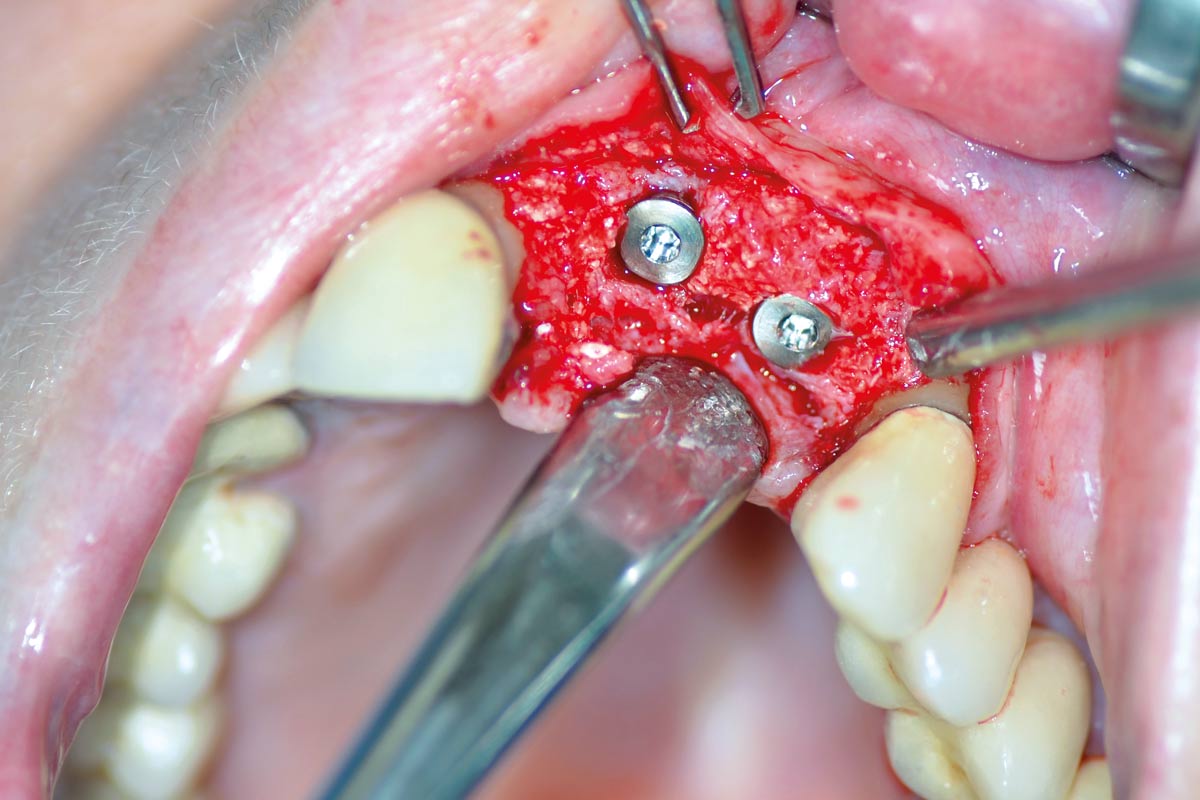

Regeneration of a 9 mm vertical bone defect with cerabone®, autologous bone and S-PRF –  Dr. A. Eslava